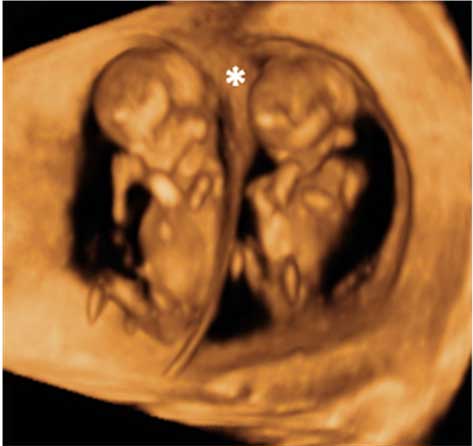

Feto de 12 semanas con cordón al cuello

Circular de cordón umbilical (en color sepia) alrededor del cuello de un feto con una edad gestacional de 12 semanas.